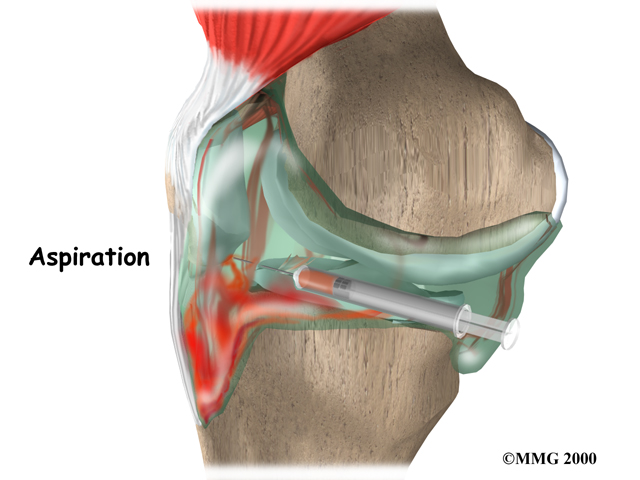

If there is fluid associated with your ACL injury, your doctor may need to place a needle in the swollen joint and aspirate (drain as much fluid as possible) the give relief from the swelling. The procedure also provides useful information to your doctor. If blood is found when draining the knee, there is about a 70 percent chance it represents a torn ACL. This fluid can also show if the cartilage on the surface of the knee joint was injured.

Aspiratation